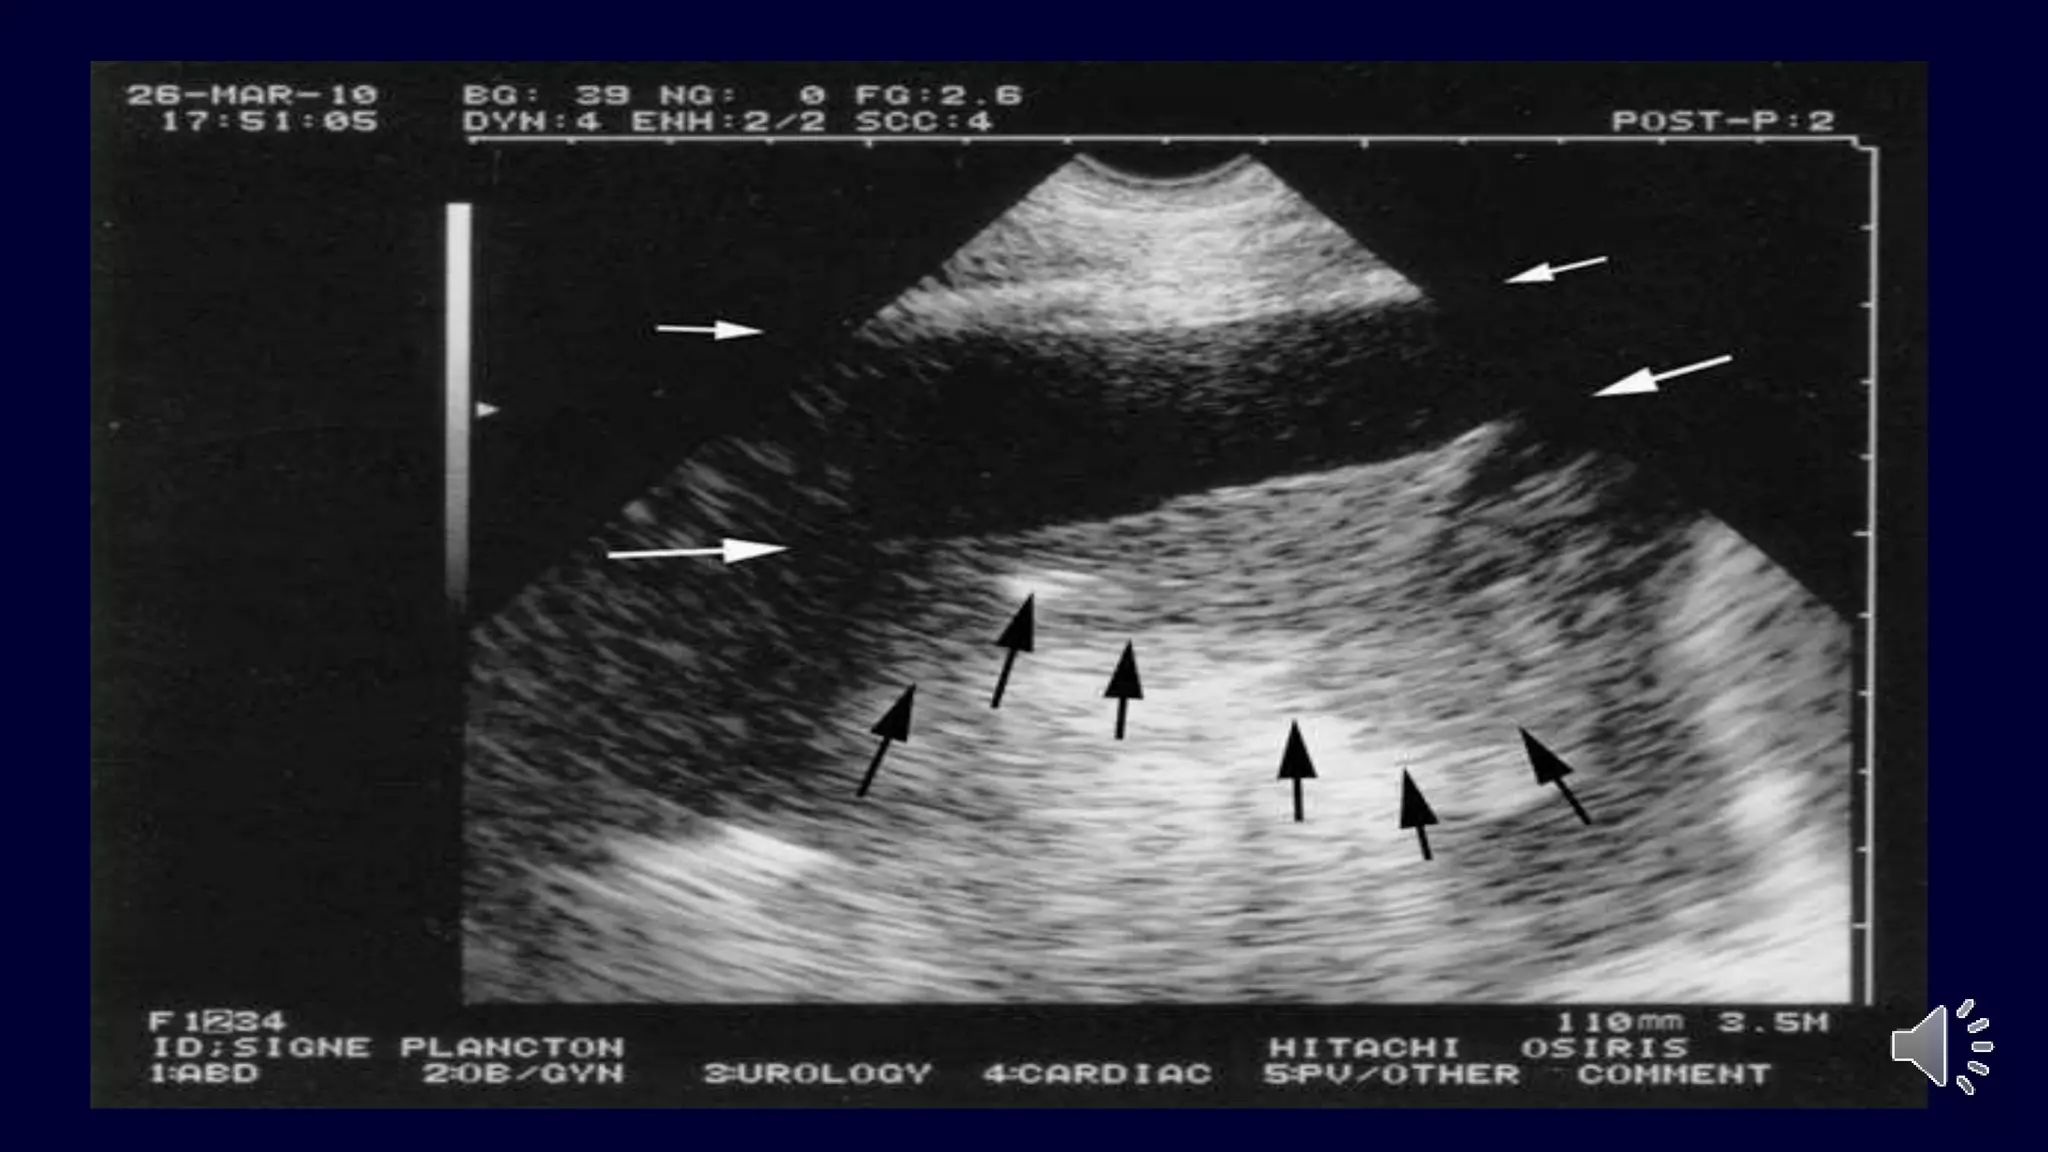

A lines = default normal

 Horizontal echo

reflection at exact

multiples of intervals

from surface to

bright reflector.

 Dry lung OR PNTX

 Decay with depth

 Obliterated by B

pleura A

A

INTERSTITIAL SYNDROME